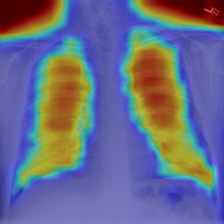

4.7.2 Activation Response Maps

As shown in Fig. 9, given the text lungs, we can find that the activation maps can accurately highlight the target regions. Therefore, we can achieve a higher performance on the downstream tasks. However, the activation maps are imperfect, as the background regions are also highlighted.